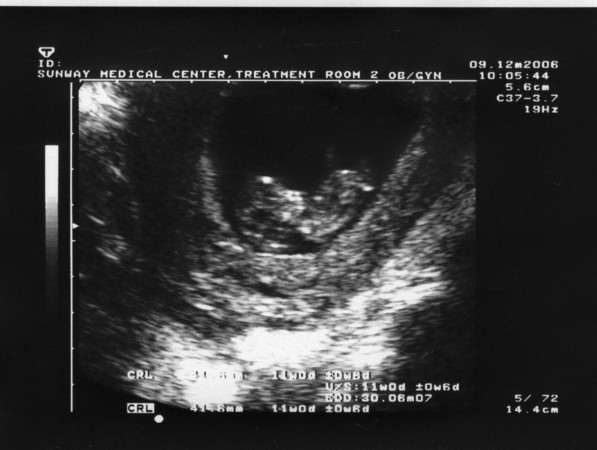

Echographie du bébé de Kanda à 4 mois (Kuala Lumpur, décembre 2006).

Echo of Kanda's baby at 4 months pregnancy (Kuala Lumpur, December 2006).